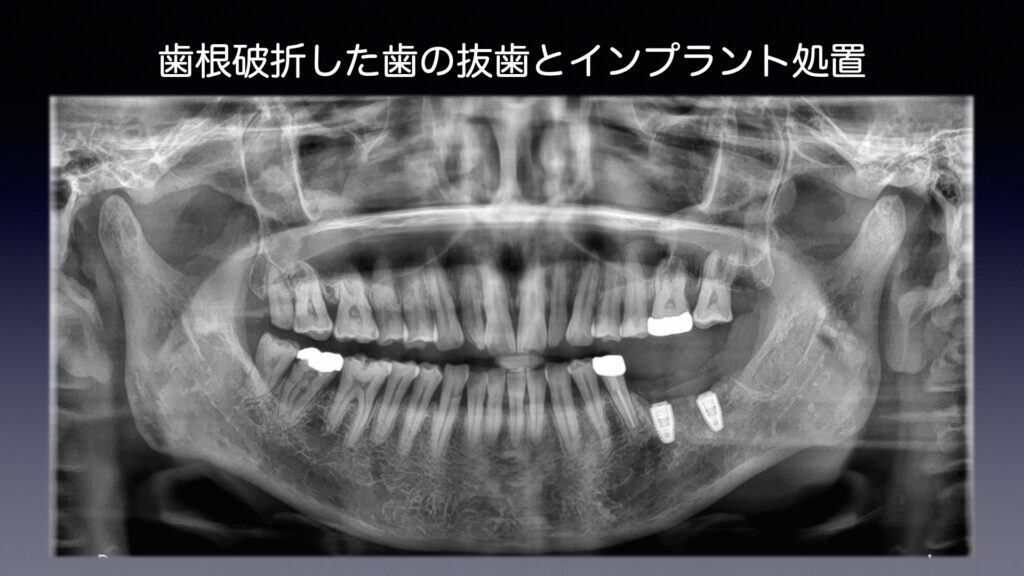

初診から治療終了までの流れ

② 過去との比較

治療した当初の状態と比較し、

変化が起きていないかを丁寧に確認します。